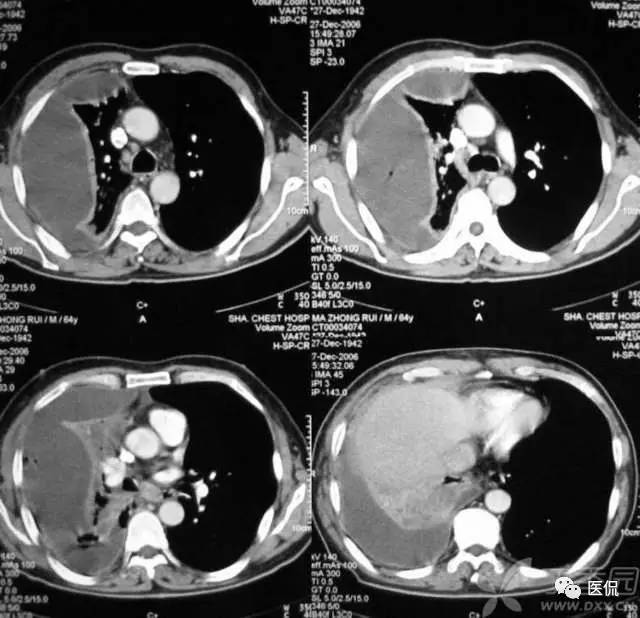

胸膜分离征

表现为胸膜脏层和壁层胸膜增厚并被其间的胸腔积液分开,当胸膜感染,胸腔内积脓时,胸膜常常有明显强化。脓胸一般继发于细菌性肺炎。在肺炎旁胸腔积液时,由于毛细血管通透性增加,液体进入胸膜腔,随着液体集聚增加,细菌透过损伤的内皮进入胸膜腔,导致胸膜腔积脓,随后纤维和内皮毛细血管在胸膜表面形成包膜并增厚。脓胸通常伴有胸膜外肋下肌组织肿胀和胸膜外脂肪变薄。